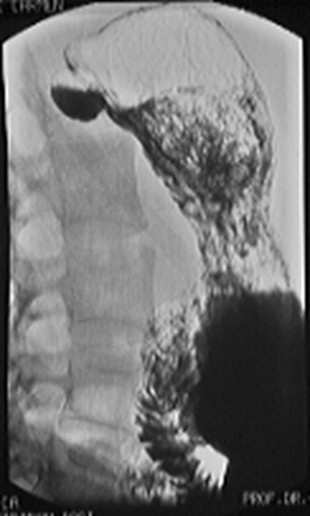

Ulcere jeune bulbaire . Image

TOGD en OAD normale et expose avec compression

region bulbaire |

Aspect en treffle une ulcere

bulbaire . Image TOGD baryte en OAD |

Aspect en etoile

d,une ulcere bulbairede l'estoma |

Image TOGD d'une ulcere

duodenal D2 |

Ulcere D2 avec dilatation duodenale et

epaissisement des plies muqueuses duodenales (

duodenite ) en aval et au amont de ulcere |